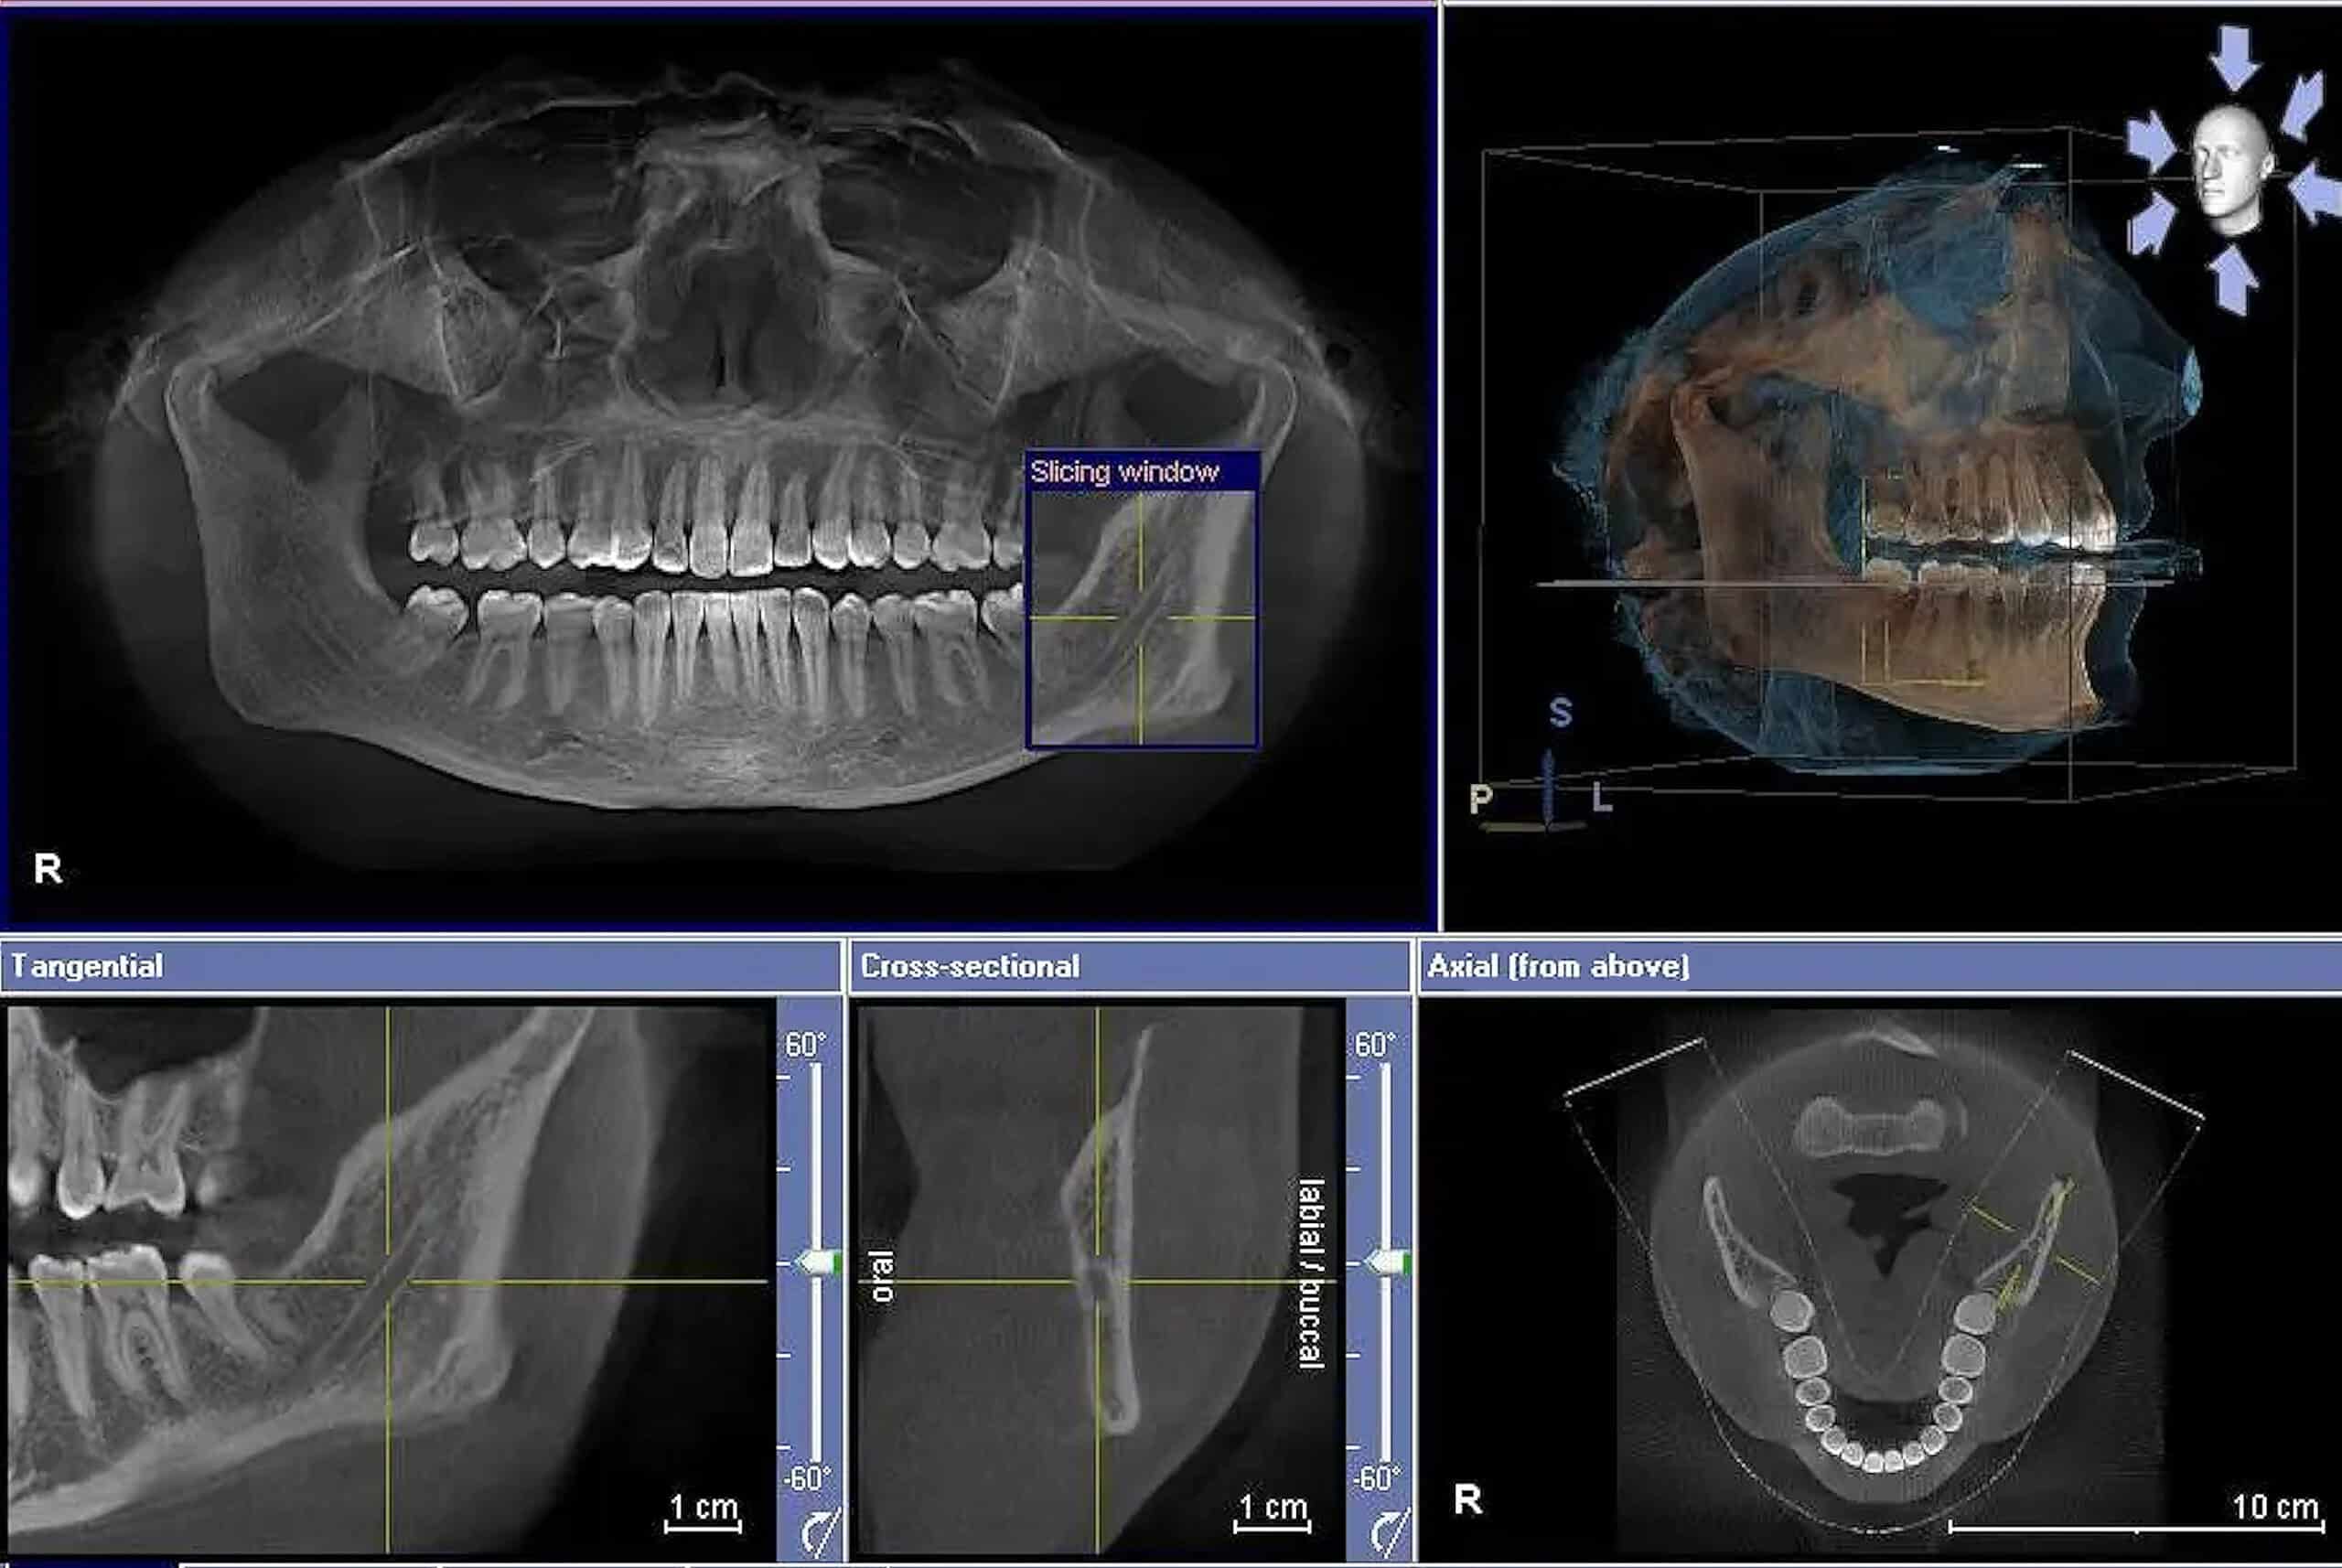

What is Dentoalveolar Surgery?

The term dentoalveolar refers to the teeth and the alveolar bone that supports the teeth. Surgery involving the dentoalveolar area is the basis for much of oral and maxillofacial surgery. Dentoalveolar procedures range from simple extractions to much more complex procedures. Often, a combination of procedures requiring extraction, modification to the bone, and/or modification of the gum tissue surrounding the surgical site is included in a dentoalveolar surgery. Dentoalveolar procedures may include a combination of the following: